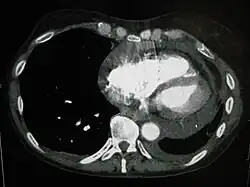

Bei großen Perikardergüssen sitzen die Patienten aufrecht, sind sehr ängstlich, haben starke Atemnot und gestaute Halsvenen, es besteht meist eine Zyanose; der Puls ist klein und weich. Durch Abklopfen des Brustkorbs kann nur ein sehr großer Erguss festgestellt werden.[3] Die einfachste und schnellste Methode, um einen Erguss zu erkennen, ist der Ultraschall. Auch im CT kann man einen Perikarderguss gut sehen. Die Flüssigkeit des Perikardergusses kann man zytologisch auf maligne Zellen und auf Bakterien untersuchen. Die Punktion des Herzbeutels ist technisch nicht einfach. Je größer der Erguss ist, desto einfacher und zugleich wichtiger ist die Punktion.